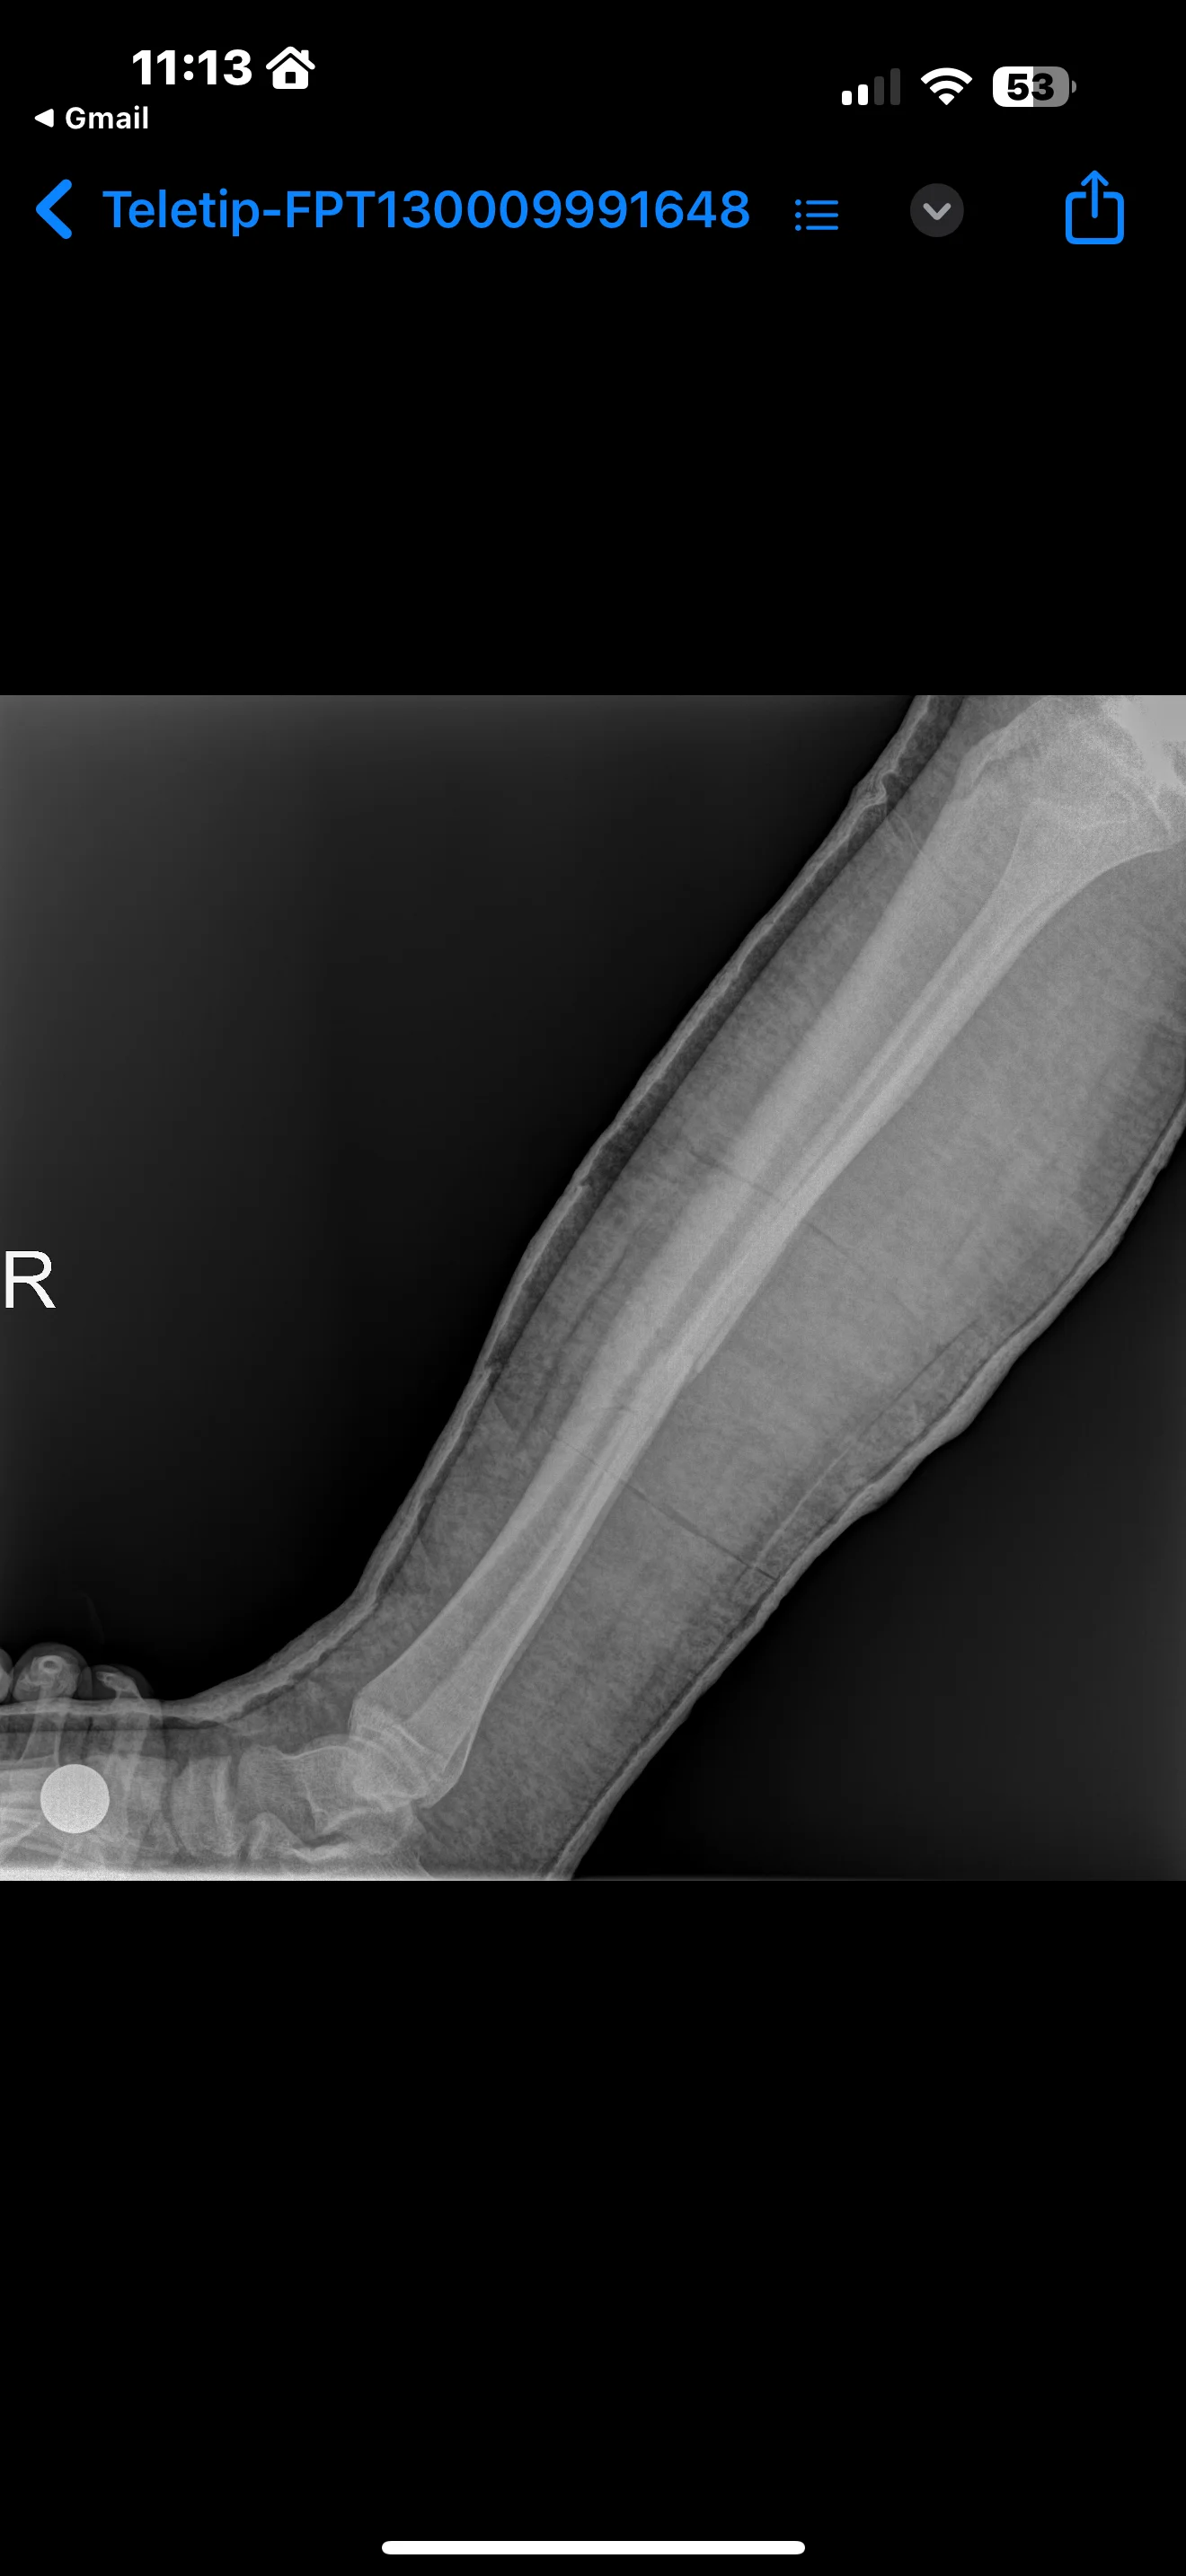

Arkadaşlar bacağım daki kaval kemiği ve yanındaki ince kemik çapraz şekilde araba ezmedi sonucunda kırıldı yaşım 17 yaklaşıl 1 ay 6 gündür yatıyorum ve hala iyileşmedi daha önce böyle bi durum yaşayan oldu mu pazartesi günü çektiğim röntgenler bunlar doktorum bana yaşından dolayı ameliyat tan kurtuldun dedi 1 ay daha alçıda kalacak dedi ve bu kırk açık yaralı kırk tı yani derimde 1 cm lik bide yara açtı oraya da 6 dikiş atıldı dikişler de alındı

• IMG_6476.webp

IMG_6476.webp

99.4 KB · Hit: 108

• IMG_6477.webp

IMG_6477.webp

105.5 KB · Hit: 110